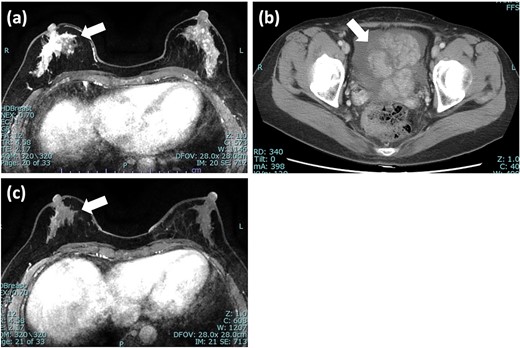

A 55-year-old woman was diagnosed with invasive lobular carcinoma (ILC) in her right breast (Fig. 1a). Breast biopsy revealed Luminal A subtype with positive estrogen-receptor (ER), progesterone-receptor (PgR), negative HER2 expression, and low Ki-67 index (5%) (Fig. 2a). She received neoadjuvant chemotherapy, which comprises two cycles of epirubicin plus cyclophosphamide (EC) therapy. However, a left salpingo-oophorectomy was carried out after a computed tomography (CT) scan identified an ovarian tumor, which was assumed to represent the primary disease (Fig. 1b). She was diagnosed with ovarian metastasis from breast cancer after histopathological samples of her left ovary revealed the same pattern as the breast cancer. She was treated with chemotherapy (docetaxel; DTX) and hormonal therapy (anastrozole), which led to a clinical complete response (cCR) for the breast cancer lesion (Fig. 1c).

Imaging tests of right breast cancer and ovarian tumor. (a) MRI of the breast showed heterogeneous enhanced lesion below the nipple; (b) CT scan of pelvis revealed an ovarian tumor with increased ascites; (c) MRI after 5 months showed significant reduction in the size of tumor and diminished enhancement. MRI: magnetic resonance imaging; CT: computed tomography.